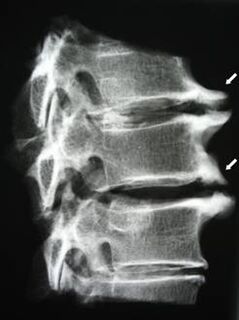

În stadiile inițiale, osteocondroza este detectată prin RMN. Mai târziu, patologia poate fi diagnosticată folosind radiografie. Pe radiografiile coloanei cervicale, devin vizibile o scădere a distanței dintre vertebre, modificări patologice ale articulațiilor fațetelor și osteofitoza.

Mulți oameni se plâng că nu își pot întoarce gâtul din cauza durerii severe care apare după ce ridică brusc ceva greu. Acest fenomen indică formarea unei hernie de disc. Cauza durerii în spate, gât și membru superior este ciupirea uneia dintre rădăcinile nervoase care ies din măduva spinării.